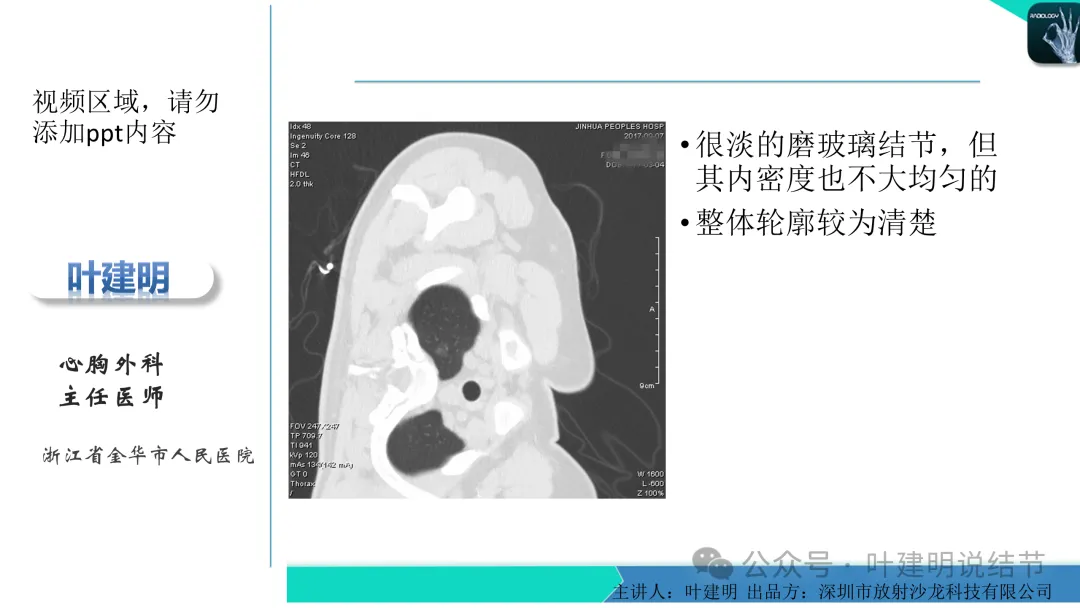

早在2020年时,我受邀在《放射沙龙》做过一个系列的精品课,当时专门总结分析过各类良恶性肺结节与肿块的影像特征,这是当时关于微浸润性腺癌影像特征的分析,今天看来仍基本不太需要改变,大家有兴趣的可以参考: